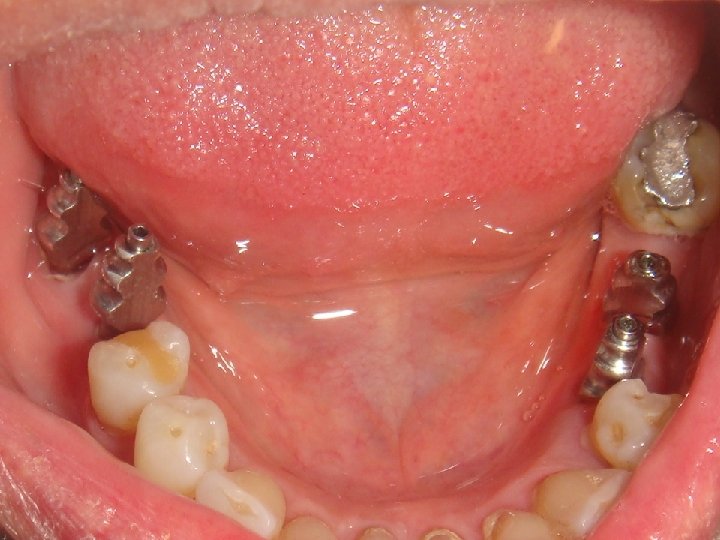

Title No. 2: Innovative Prosthodontics based on a high load capacity of implants

Abstract No. 2: Modern concepts of implant Prosthodontics emphasises an optimal simulation of the lost oral tissues – tooth, bone and soft tissue. The quality of simulation can be defined by several parameters, e. g. the dimension of an occlusal surface, the used dental materials, the type of fastening of the suprastructure, etc.

Abstract No. 2: (cont. . ) Planning implant Prosthodontics is mainly related to the available amount of residual bone and the load capacity of an implant. Especially the bone anchorage and the component strength of an implant limit the construction design of a suprastructure. Therefore to gain a deep insight into biomechanics is a prerequisite for an adequate planning of an appropriate construction design. In case of very high load capacity of an implant the expanded treatment possibilities are: • unsplinted single posterior crowns • physiological occlusal surface • long cantilevers • inclusion of patients with excessive bruxism • short implants • small implant diameter

Abstract No. 2: (cont. . ) The important consequence in the daily work of the last two items - the ability to use short and small implants due to an excellent bone anchorage - is a reduced need of augmentation procedure resulting in a huge increase of patients which accept implant based therapies only with minimal invasive medical intervention. However, an aesthetic result borne on a small implant-diameter requires a creative implementation on the part of the dental technician, taking the surrounding soft tissues (emergence profile) into due account. The submucosal shape of the abutments or the crown should correspond to a natural tooth and should be designed like an ovate-pontic of a bridge.